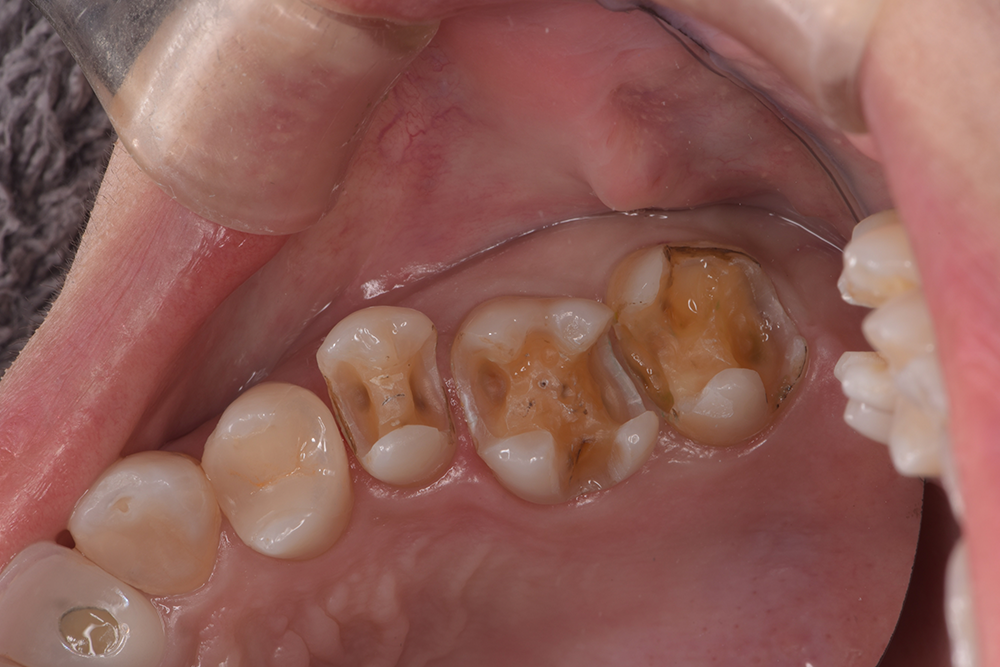

| 治療経過 | 銀歯の隙間にフロスが引っかかるとのことで治療介入となった。 銀歯の下は全て虫歯になっており、今後虫歯のリスクを軽減させることを目的として、歯への接着力、清掃性に優れたセラミックを用いた修復方法を選択した。 |